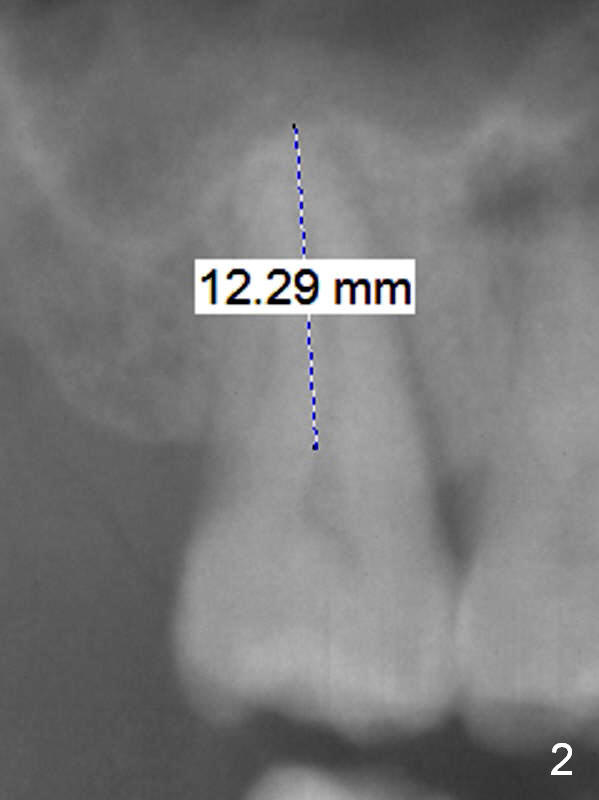

A 53-year-old man agrees implant treatment for crack tooth #2 (Fig.1). Since the apex overlaps the sinus floor (Fig.2 panoramic X-ray), the primary stability will be derived from tight contact of an implant with the socket. After extraction (Metronidazole), osteotomes are going to be used to break through the sinus floor (RT2-4), followed by tap drills (4.5 mm or larger (Fig.3) until achieving 35 Ncm). The implant will be one size larger. Prepare regular and extra wide surgical kits. Before implant placement, insert PRF plug and allograft/Osteogen.